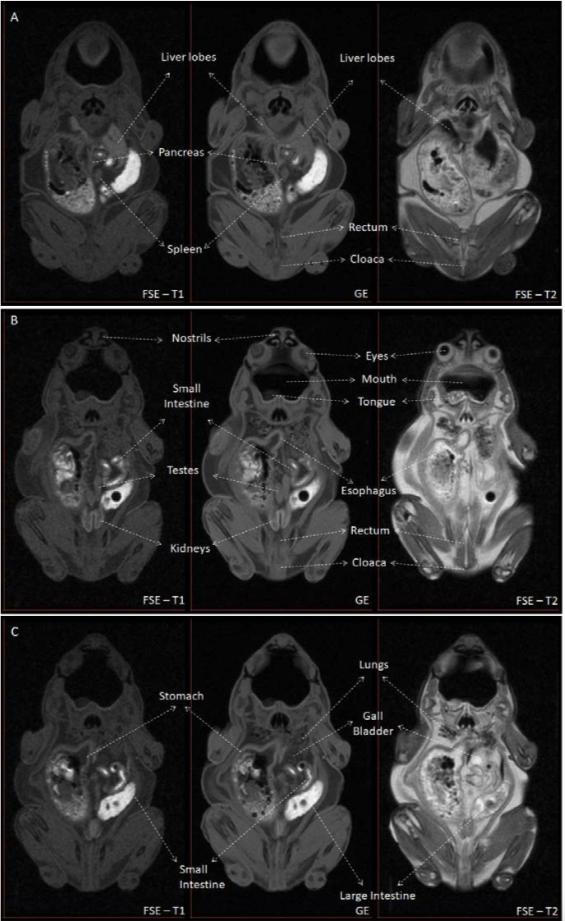

Figure S1 - MRI identification of structures contained in the coelomic cavity. Figure S1 shows the main structures identified in the coelomic cavity in Kaloula pluchra frog. Three different slices of the MRI experiment were selected (A, B, C). Three different MRI weightings (Fast Spin Echo T1-weighted, Gradient Echo and FSE T2-weighted) are shown for each slice. |